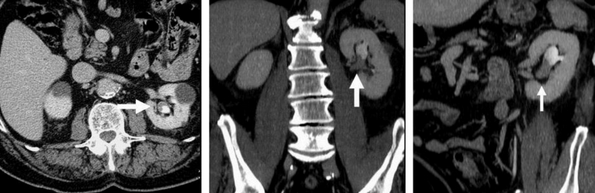

КТ в разных проекциях показывает опухоль в левой почке (стрелка)

КТ органов мочевыводящей системы с усилением

Контрастирование требуется не всегда, введение препарата необходимо при:

первичной оценке опухоли — пораженные и нормальные ткани выглядят по-разному, что важно для определения стадии онкологического процесса;

подозрении на рецидив рака после лечения — контрастирование помогает уточнить характер изменений в лимфатических узлах, дифференцирует фиброзную дегенерацию после операции и продолженный рост;

начальной стадии заболевания, когда изменения выражены незначительно;

проведении комплексного урологического исследования — КТ мочевыводящих путей показывает функцию каждой почки в отдельности, препятствие к оттоку урины на любом уровне, патологические рефлюксы, кисты и пр.